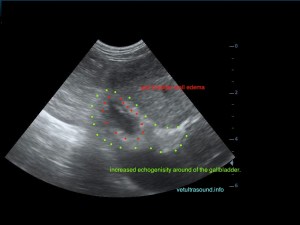

Ήπια ηπατομεγαλία με αύξηση της ηχογένειας του οργάνου, χωρίς παρουσία εστιακών αλλοιώσεων(pic.4). Πάχυνση του τοιχώματος της χοληδόχου κύστης με εικόνα βλεννοκήλης ( kiwi sign) και έντονη υπερηχογένεια στη περιοχή περί αυτού(pic.1&2). Ήπια διάταση της νεφρικής πυέλου, πιθανόν λόγω της πολυουρίας και πολυδιψίας(pic.3). Επασβέστωση στον οπίσθιο πόλο του δεξιού επινεφριδίου και αύξηση των διαστάσεών του(pic.6). Απουσία ασκιτικής συλλογής και παθολογικά διογκωμένων λεμφαδένων.

Η διάγνωση μετά τον υπέρηχο τέθηκε ως βλεννοκήλη της χοληδόχου κύστης με εικόνα χολοκυστίτιδας σε υπόβαθρο πιθανού υπερφλοιοεπινεφριδισμού. Θα πρέπει να γίνει επιβεβαίωση με αιματολογικές εξετάσεις του υπερφλοιοεπινεφριδισμού, καθώς η βλεννοκήλη της χοληδόχου κύστης είναι μία από τις επιπλοκές αυτού.